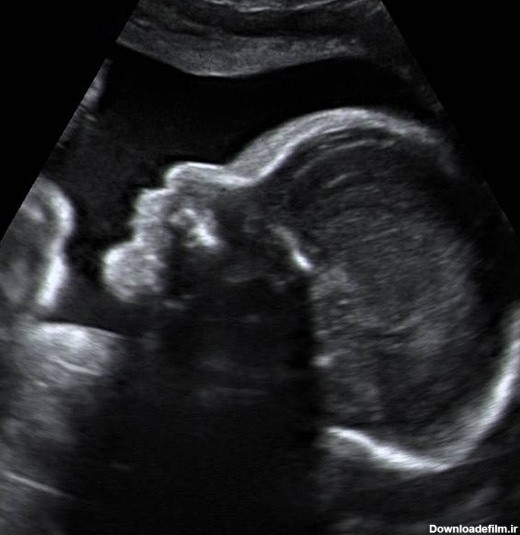

عکس جنین پنج ماهه پسر در شکم مادر

در این متن ضمن مشاهده عکس جنین در هفته بیست و هفتم بارداری اطلاعاتی را درمورد بهترین میوه برای دوران بارداری کسب خواهید کرد.

بدن هر مادر در طول بارداری تغییرات متفاوتی دارد. یکی از تغییرات مهم مرتبط با بزرگتر و قابل مشاهده شدن شکم مادر در ماه پنجم بارداری است.